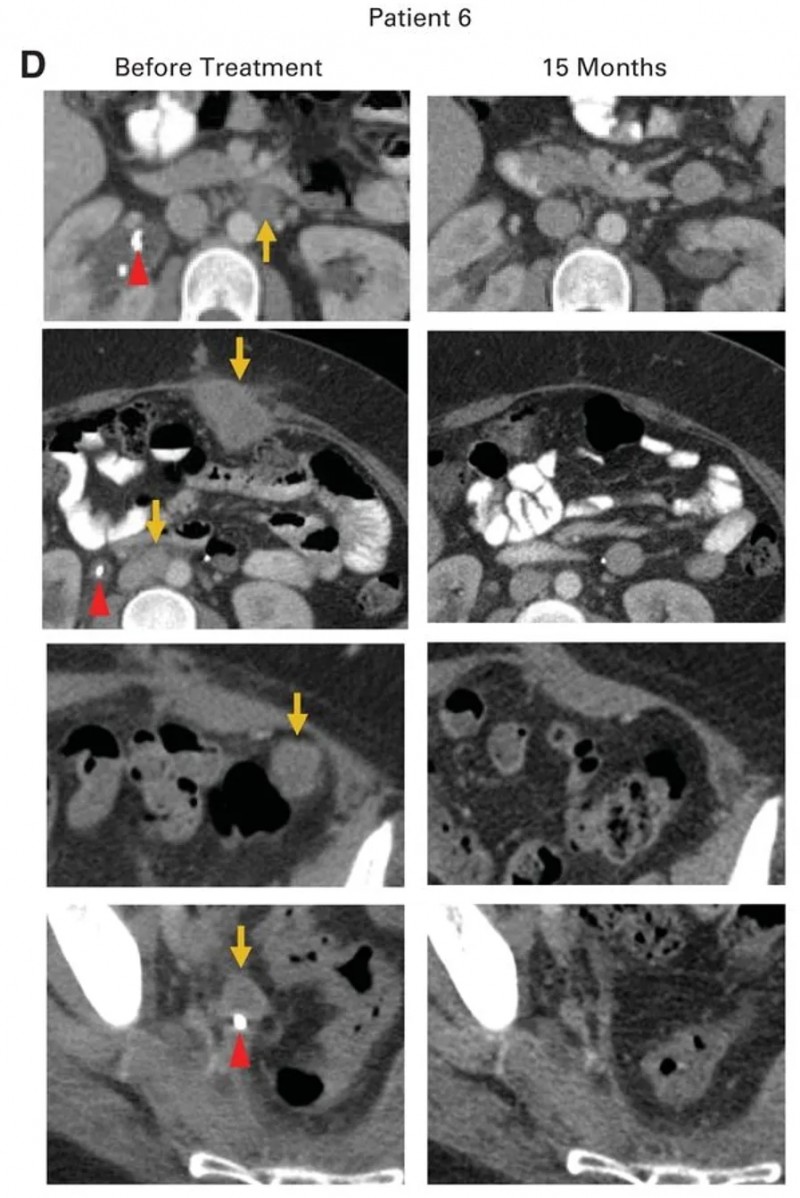

患者6(转移性腺癌):原发肿瘤对放化疗无应答,经挽救性手术后病情仍持续进展,累及腹膜后淋巴结、肝脏表面等部位,伴右侧输尿管肾积水、双侧肺栓塞,需依赖输尿管支架及抗凝治疗。HPV-TIL治疗前,腹膜后、腹壁、结肠旁等多处肿瘤仍在进展。治疗后达成完全临床缓解,15个月时无疾病迹象,右侧输尿管支架已移除(详见下图D)。

▲图源“ASCO”,版权归原作者所有,如无意中侵犯了知识产权,请联系我们删除